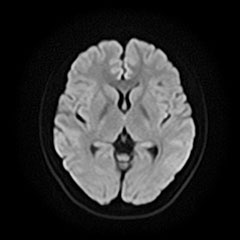

本検査により脳梗塞・脳腫瘍・脳動脈瘤・血管の狭窄/閉塞・脳動静脈奇形の有無などを確認出来ます。

脳卒中、脳腫瘍、脳萎縮、白室病変、脳室拡大

MRA

脳動脈瘤、血管狭窄、血管閉塞、脳動静脈奇形、もやもや病